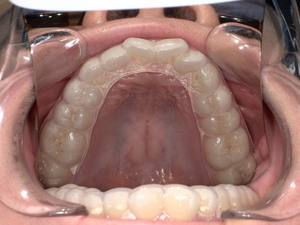

治療内容|保険適用マウスピース(ナイトガード)

患者様専用の

👉 オーダーメイド型マウスピース

を作製しました。

市販のマウスピースとは異なり、

👉 噛み合わせ

👉 顎関節の位置

👉 筋肉のバランス

を精密に設計しています。

治療結果(約3週間後)

・歯ぎしり音の消失

・歯の摩耗の進行停止

・睡眠の質向上

・肩こりの軽減

マウスピースがクッションとなり、

歯や顎へのダメージを大幅に軽減できました。